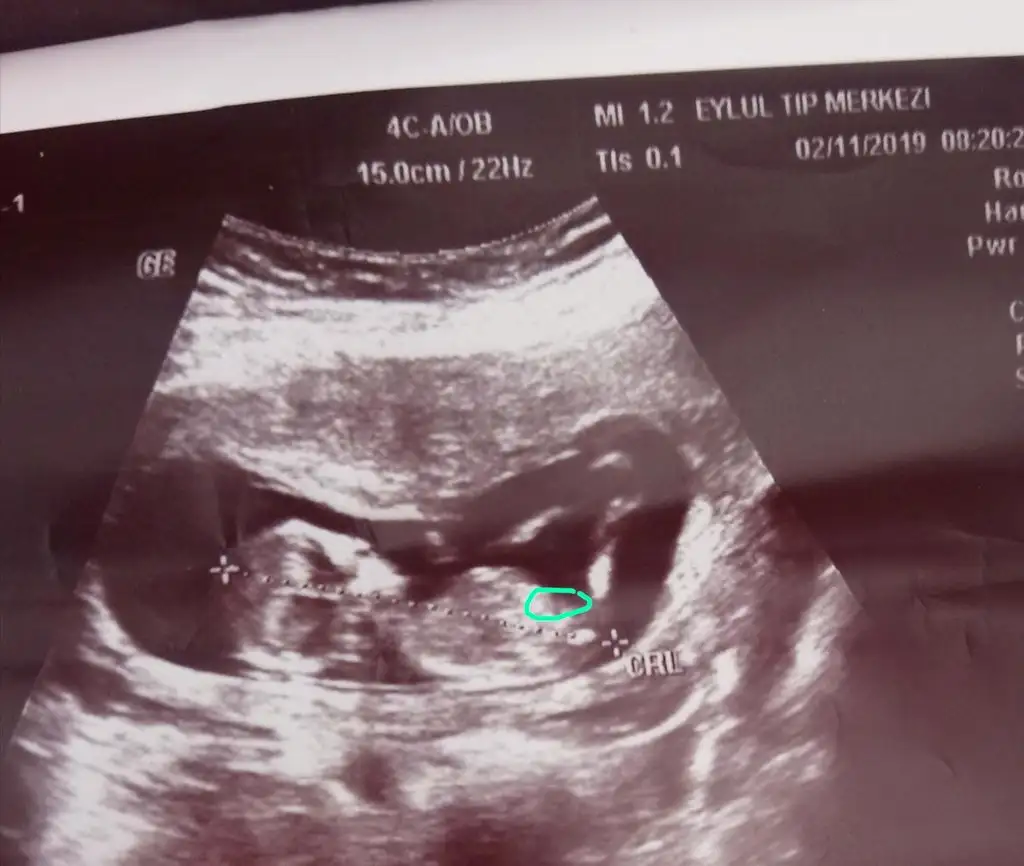

Kizlarr buda benim minik anliyan arkadaslar lutfen bi yorumlayin

• E1EB213F-78DB-40F9-8FB4-2034F2D4B51F.webp

E1EB213F-78DB-40F9-8FB4-2034F2D4B51F.webp

54,7 KB · Görüntüleme: 84